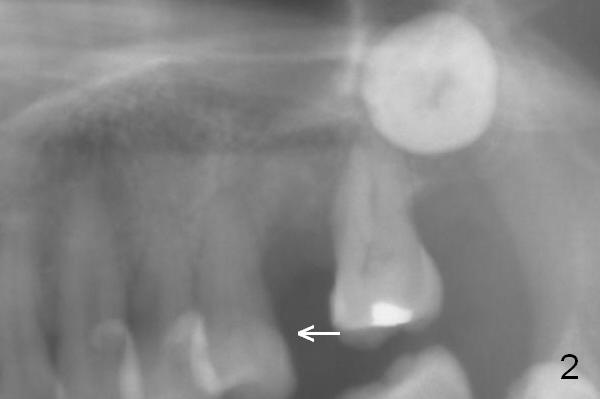

A 54-year-old woman had #14 extracted in China 1 year ago (Fig.1,5). The tooth #15 has undergone mesial shift and tilt (Fig.2,4, as compared to Fig.3). The edentulous space is too narrow for implant placement (Fig.6). It appears that traditional orthodontic appliance should be placed from UR6 to UL7 in addition to a mini-implant distal to UL7. Take Alginate impression before treatment. Since the implant at UR7 is placed apparently too deep, a band will be placed when it is initially osteointegrated (6-8 weeks postop). Fabricate a well-fit provisional with permanent cementation before banding. In fact, brackets and bands are placed between UR3 and UL7. In 6 months, the meisodistal space at #14 is enough to place an implant (Fig.7).